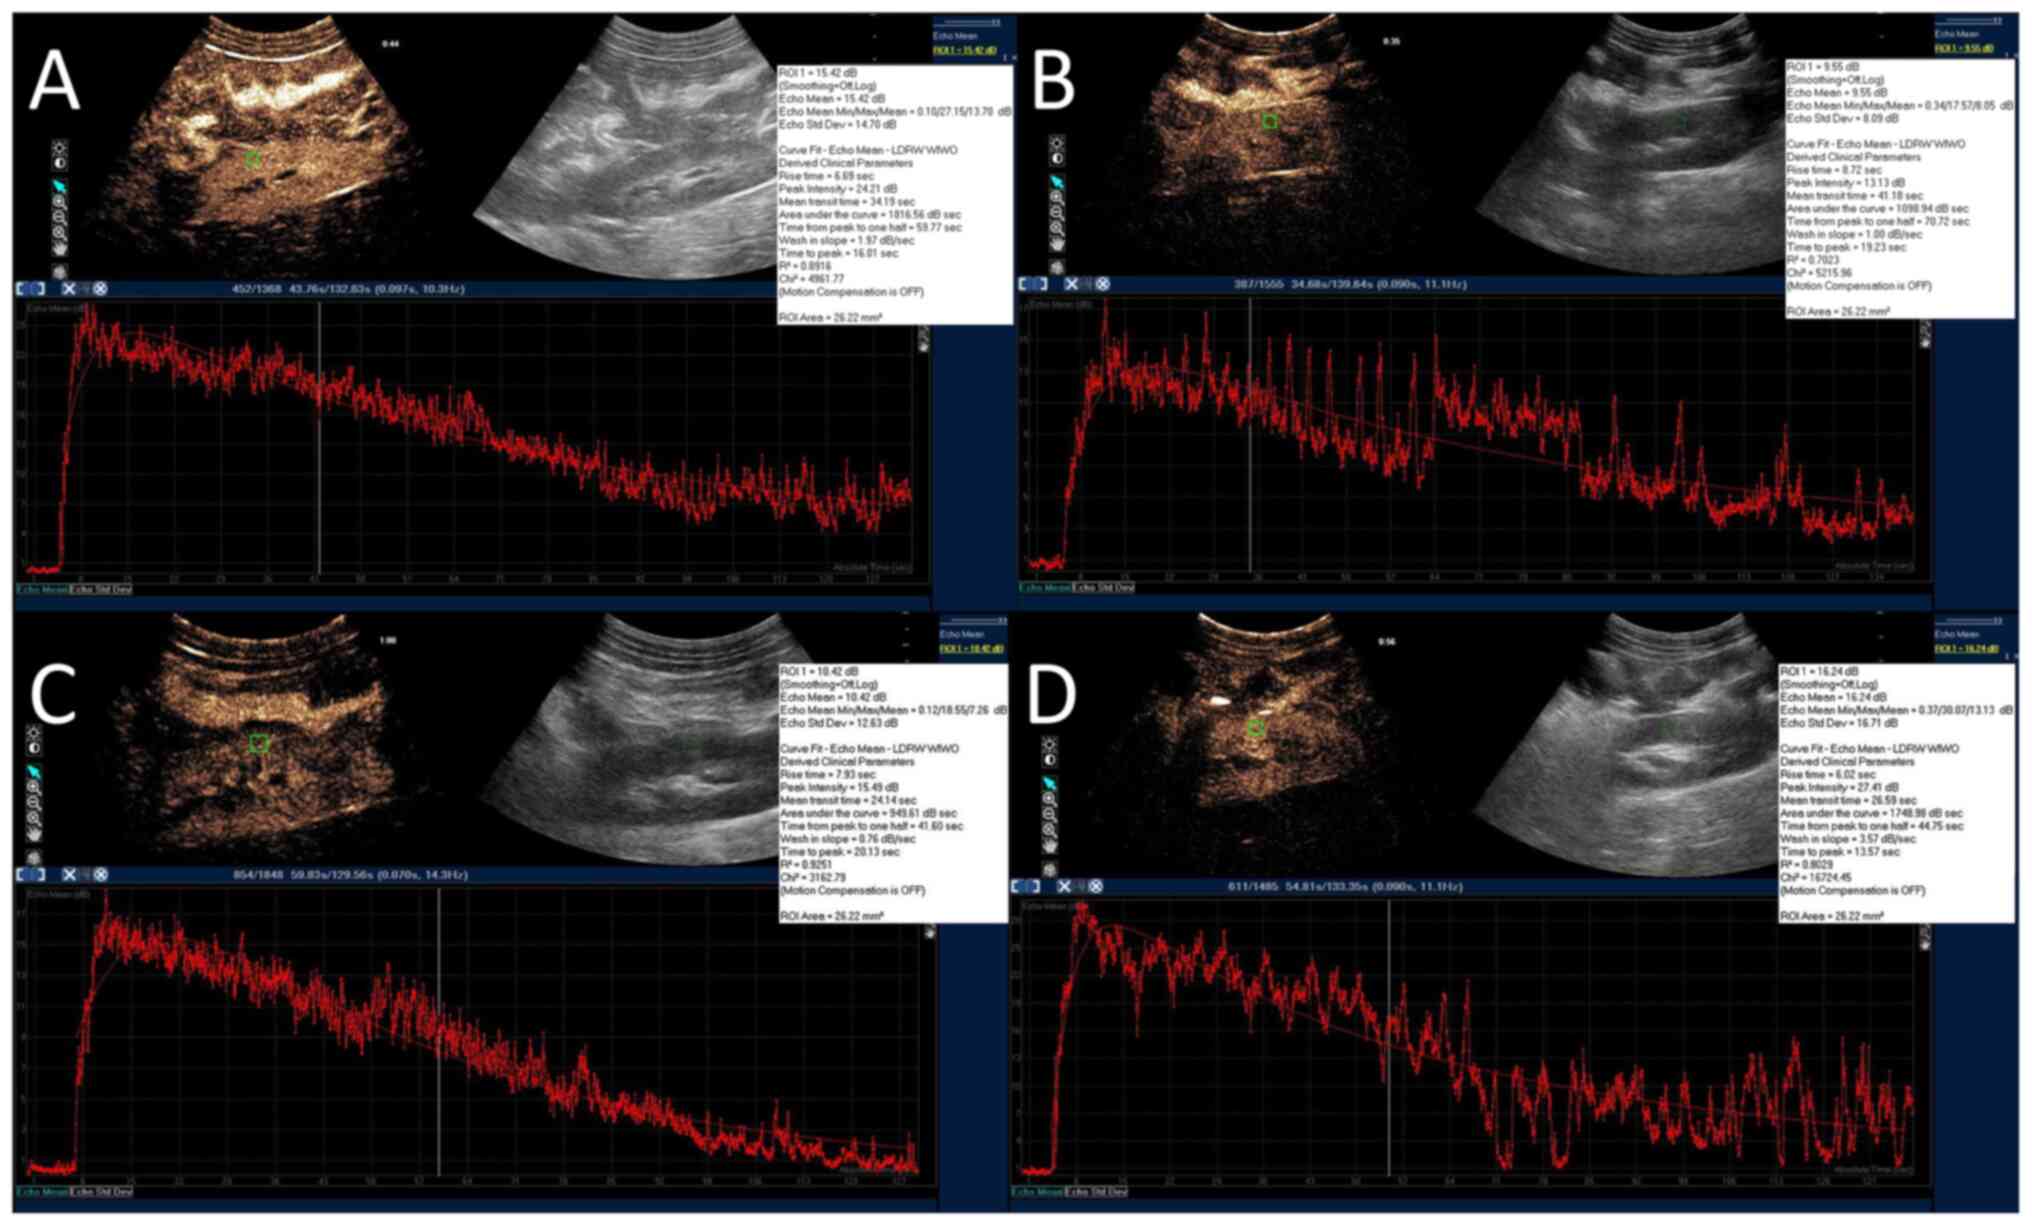

For CEUS, 2 ml sulphur hexafluoride (SF6) microbubbles (8 µl SF6/ml; SonoVue®; Bracco Suisse SA) were bolus injected via the central venous catheter. ROI (26 mm2) was manually drawn within the renal cortex to create a time-intensity curve (TIC) with the QLAB software (Philips Healthcare). The peak intensity (Pi), area under the curve (AUC), time from peak to one half (Th), time to peak (Tp) and wash-in slope (Slope) were calculated by the QLAB software automatically (Fig. 3A-D and Video S1, Video S2, Video S3 and Video S4). Three injections were done at intervals of 5 min to obtain an average value. The same renal cortex ROI was used to prevent the influence of the respiratory motion for each bolus injection.

Figure 3

Representative CEUS images. For CEUS, 2 ml sulphur hexafluoride microbubbles were bolus injected via the central venous catheter. A ROI (26 mm2; green square) was manually drawn within the renal cortex to create a time-intensity curve with the ultrasound system's QLAB software (red curves). The peak intensity, area under the curve, time from peak to 50% of maximum, time to peak and wash-in slope were calculated by the software automatically. (A) SH group. (B) SS group. (C) VAN group. (D) UTI group. CEUS, contrast enhanced ultrasound; SH, sham group; SS, septic shock group; VAN, vancomycin group; UTI, the ulinastatin group; ROI, region of interest.